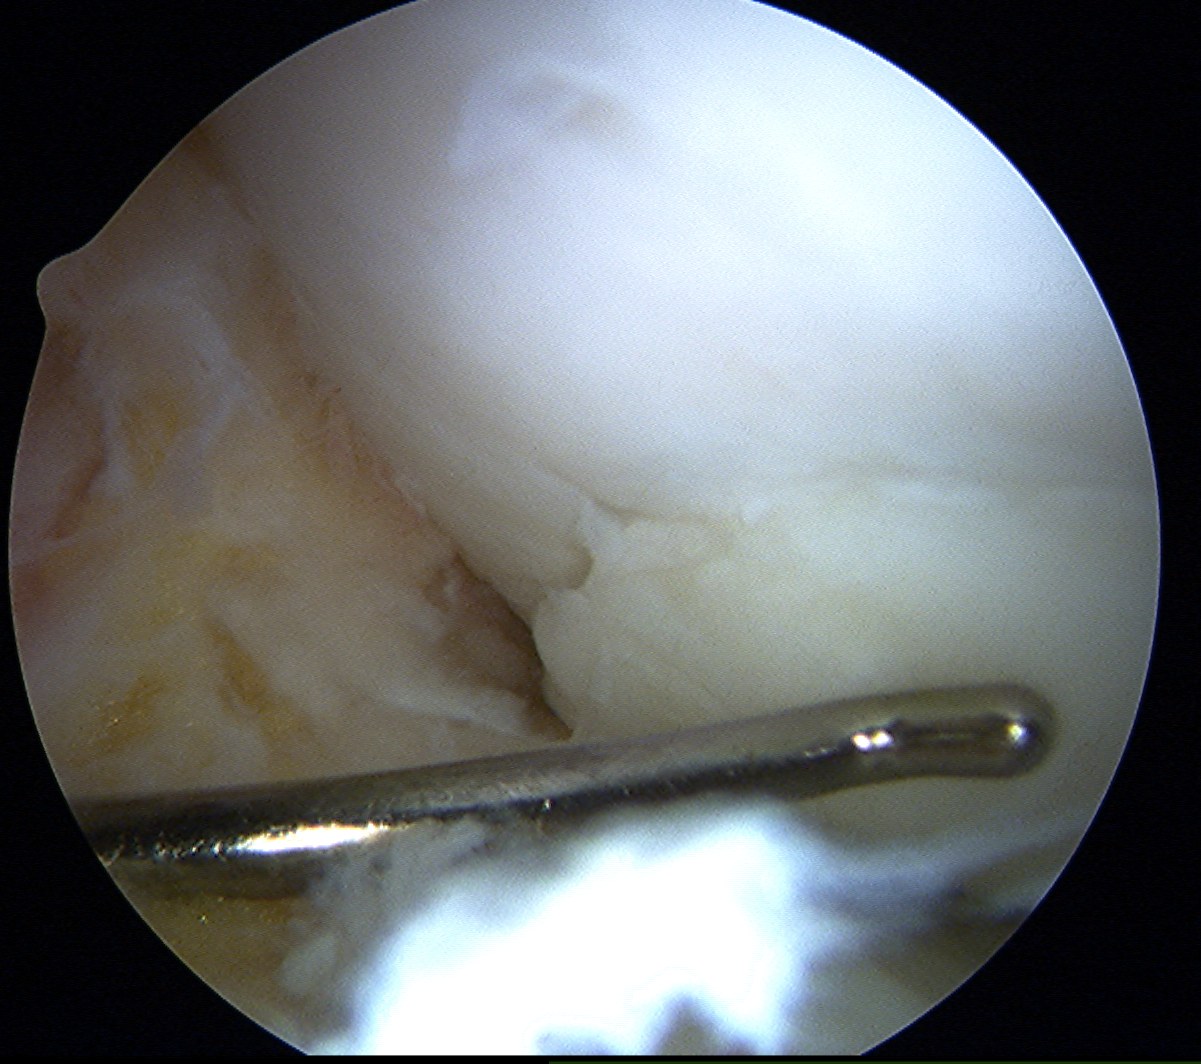

- insert plug

- use tap to insert plug

- best to countersink 1 - 2 mm

Repeat